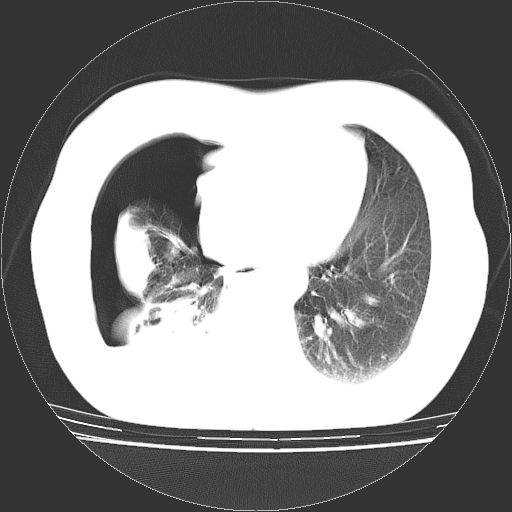

以下是引用zhangzhongshou在2008-3-22 12:52:00的发言:[br]1、右侧液气胸。[br]2、腹水。建议进一步检查。

以下是引用鲁巨ct在2008-3-22 14:10:00的发言:[br]1、右侧液气胸,右中下叶节段性不张。[br]2、腹水,建议上腹部ct检查

以下是引用zjzjr在2008-3-22 17:19:00的发言:[br]1、右侧液气胸,右下叶节段性不张。[br]2、腹水,建议上腹部ct检查